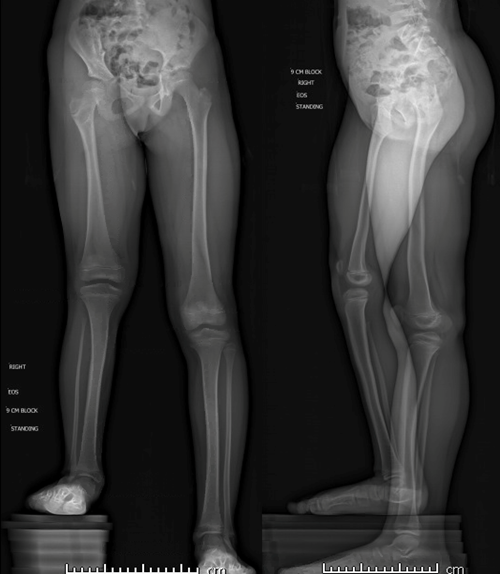

Deformity correction is the surgical adjustment or modification of bone that grows incorrectly as the result of a disease or condition, such as bowlegs or knock knee.

Spinal deformity correction surgery can be used to help patients with scoliosis, kyphosis, trauma, or other conditions that affect the spine, such as ankylosing spondylitis. Corrective surgery may also be used for conditions in which the legs, knees or ankles grow at incorrect angles or lengths.

Deformity correction is a procedure to straighten a bone that is bent or twisted in a way that is not normal. After the bone is straightened, the arm, leg, or foot has normal alignment and function. Deformities can be corrected in two different ways: